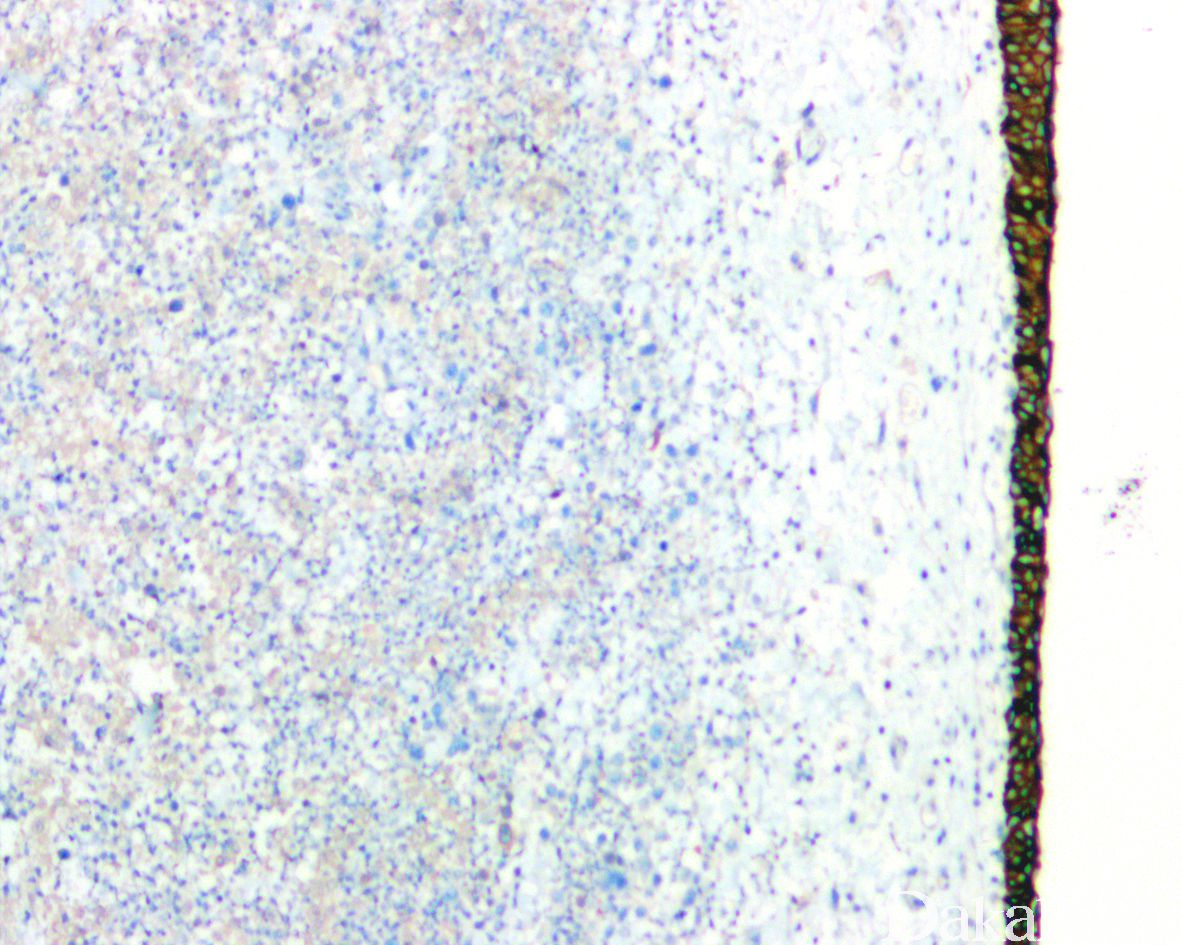

免疫组织化学染色:

浆细胞样尿路上皮癌与普通的尿路上皮癌具有相似的免疫表型特征表达 GATA3(80%),P63(45%),CK7( 92%),CK20(70%)。由于 CDH1 基因突变,浆细胞样尿路上皮癌常出现 E-cadherin 表达缺失。少数可表达 GCDFP15,PR,CDX2 等。部分可表达 CD128,需要与浆细胞瘤鉴别,但不表达 CD38 和 MUM1 等浆细胞标志物。